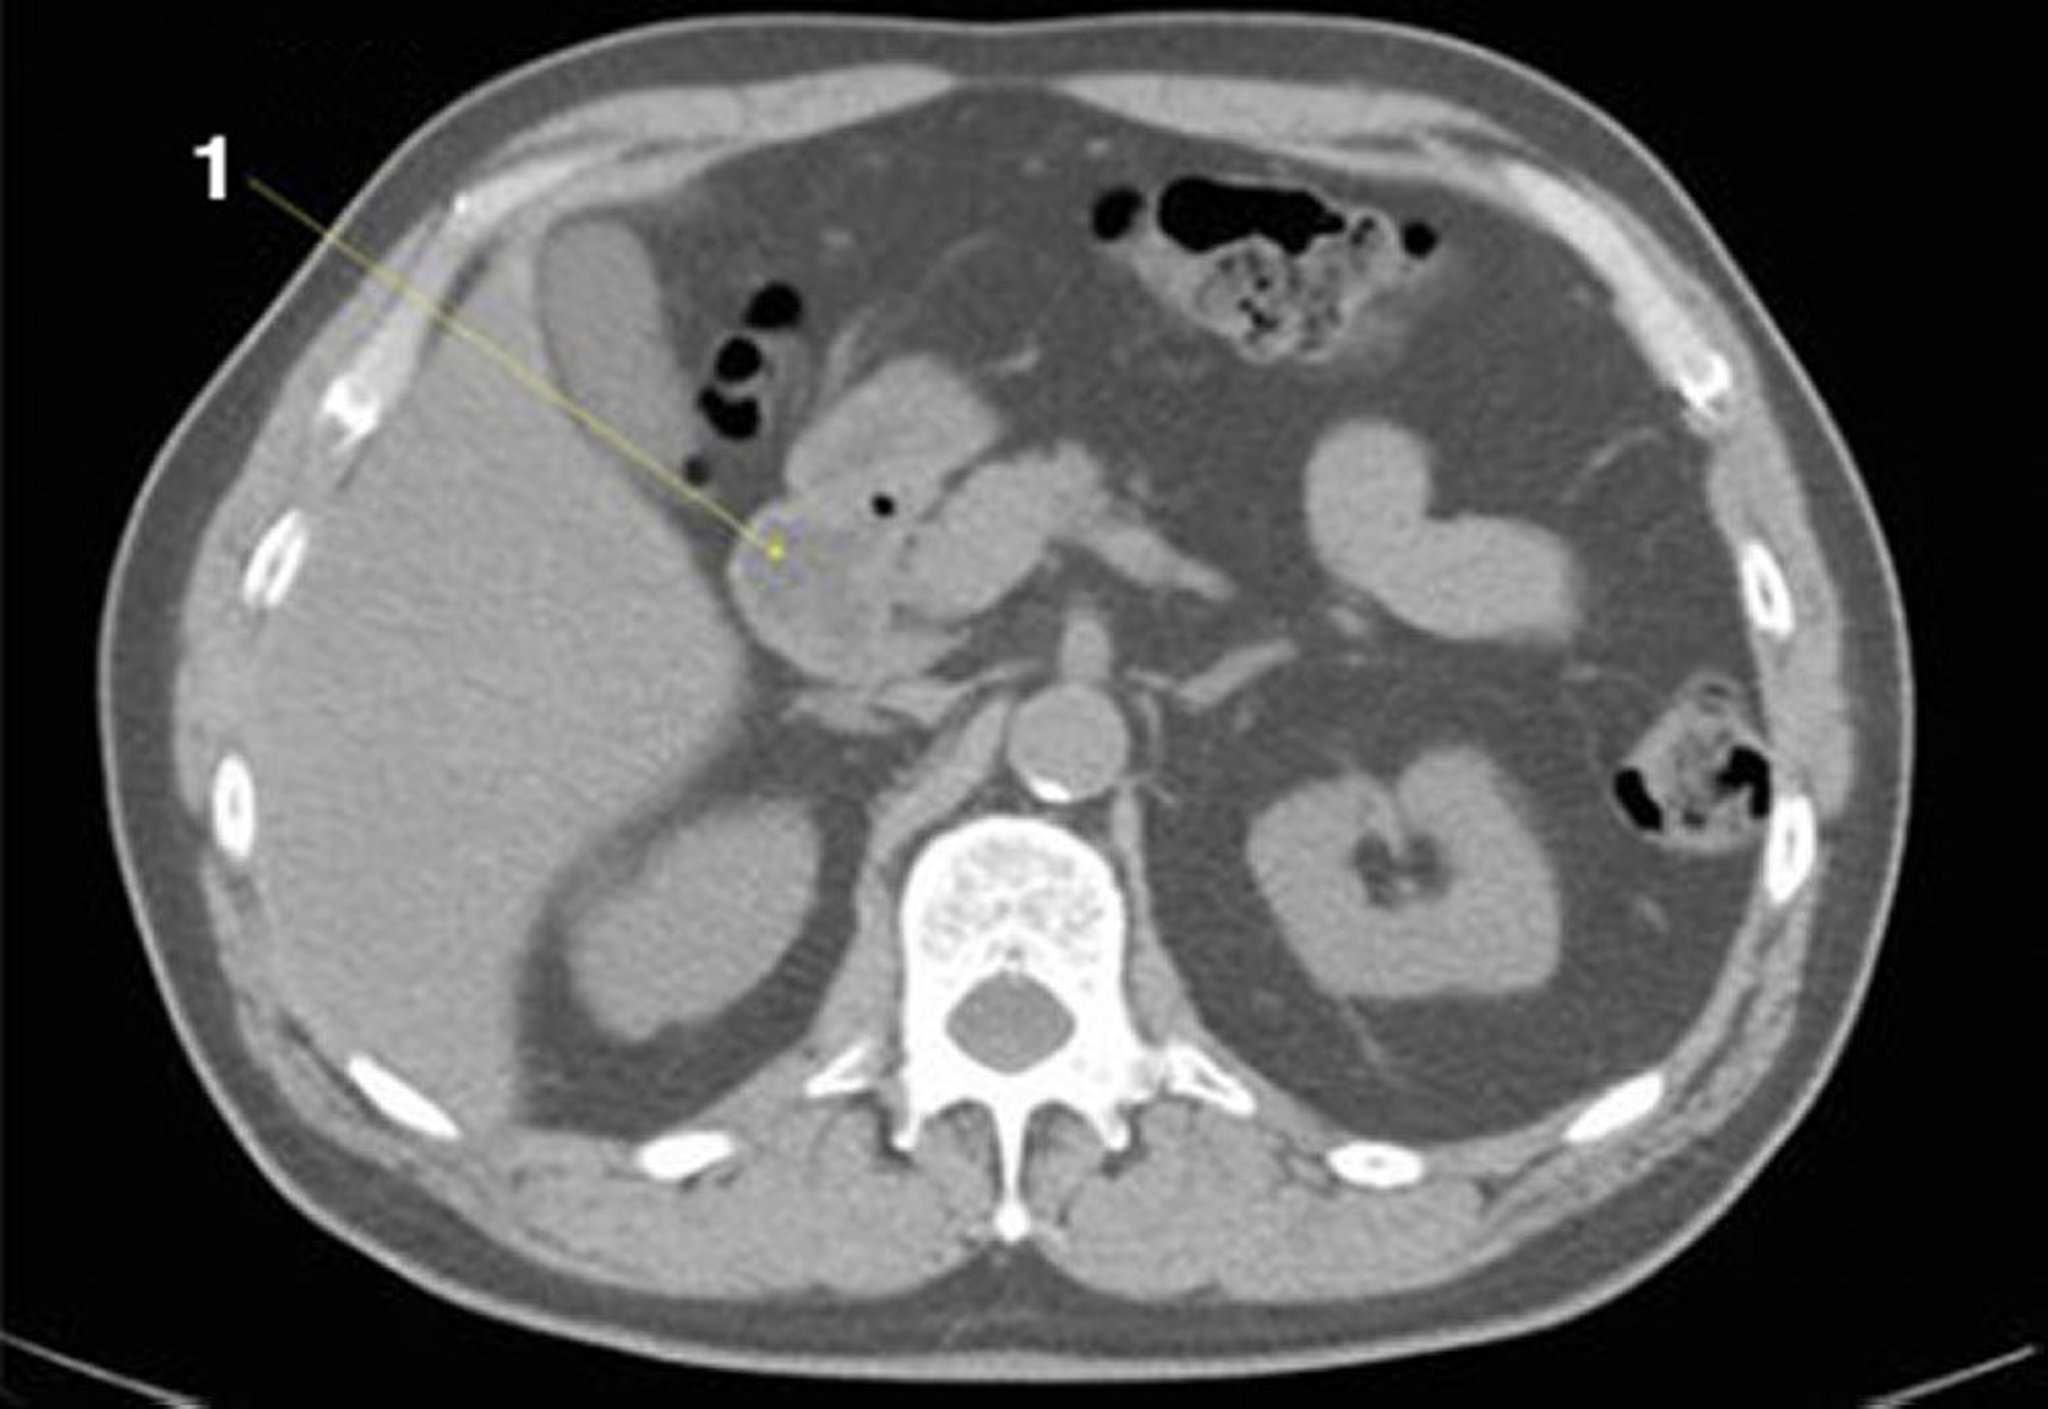

正常解剖を示した腹部および骨盤の単純CT画像(スライド11)

1 = 十二指腸。